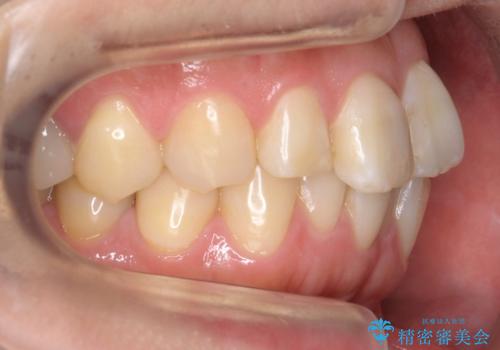

前歯の歯並びが気になる マウスピース矯正 30代女性

- 前歯の歯並びが気になることを主訴に来院された患者様です。

接客業のためインビザライン(マウスピース矯正)をご希望されました。

顎が小さく歯を並べるためのスペースが足りないため、

上下の前歯の歯と歯の間をすく処置(ディスキング)を行いました。

矯正装置:インビザラインフル (初回13stage+リファインメント11stage:計1年)

矯正後、右上5左上45セラミッククラウン・右下65左下5セラミックインレーによる補綴治療を行いました。